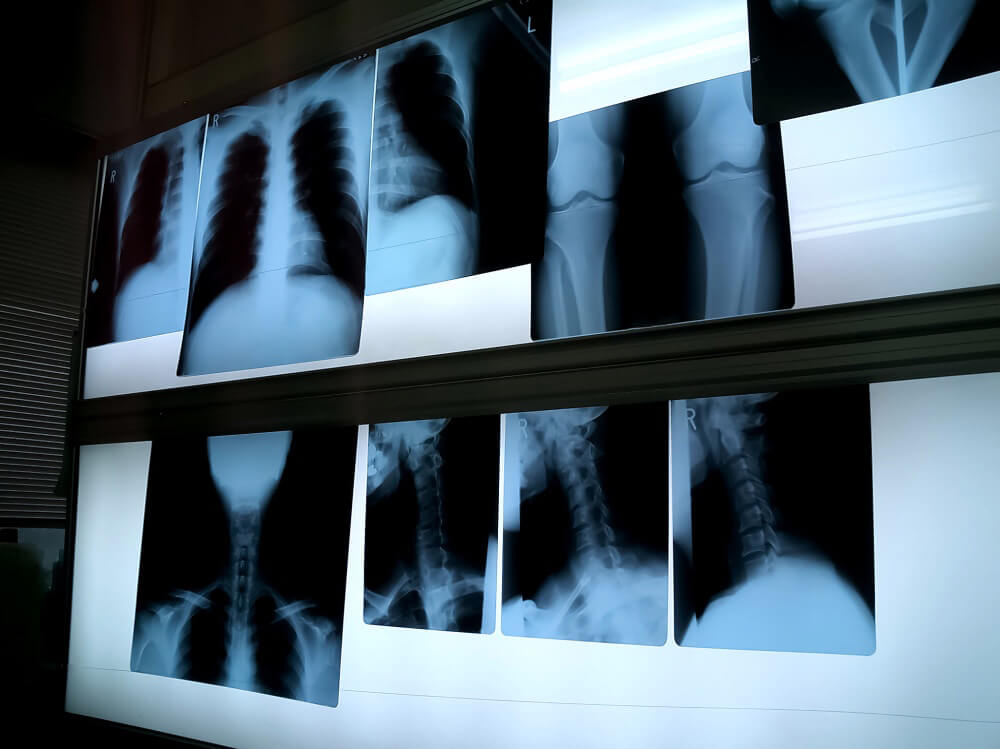

交通事故治療では、一人ひとりの症状を正確に把握し、最適な治療を行うために、検査や診療の流れが決まっています。特に、目に見えない体の不調を扱うため、レントゲンやMRIなどの画像診断を使った精密な検査が必要となります。

画像診断

骨折や脱臼の有無を確認するため、レントゲン検査を行います。また、むちうち症の場合は神経や椎間板の状態を詳しく確認するため、CT・MRIなどの検査が必要になることもあります。画像検査の結果は、症状の程度を判断し、治療の方針を決める基礎となります。

A.画像診断や神経学的検査を通じて状態を確認します。レントゲンでの骨折の有無を確認したり、しびれや神経症状がある場合はCT・MRIで詳しく調べます。